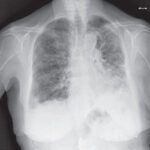

La intoxicación por bloqueadores beta-adrenérgicos es un fenómeno clínico complejo que se asocia a la administración excesiva o inadecuada de fármacos que actúan sobre los receptores beta-adrenérgicos del sistema nervioso…